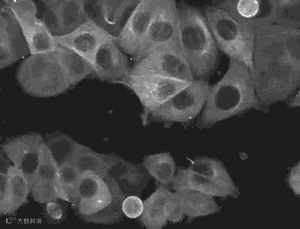

那么什么是间充质干细胞呢?间充质干细胞是干细胞家族的成员,具有自我复制能力和强大分化潜能。同时,间充质干细胞拥有其他干细胞所没有的优点,那就是它还独有向损伤组织定向迁移并根据具体环境来调节免疫反应的能力,这使其在临床应用上表现了巨大的潜力。针对间充质干细胞的这些特性,目前国内外的科学家们已经在间充质干细胞领域开展了深入的科学研究,以期充分了解和认识它强大的可塑性。